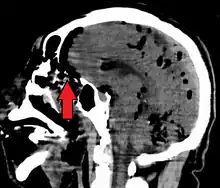

Large pneumocephaly secondary to surgical wound

Pneumocephaly